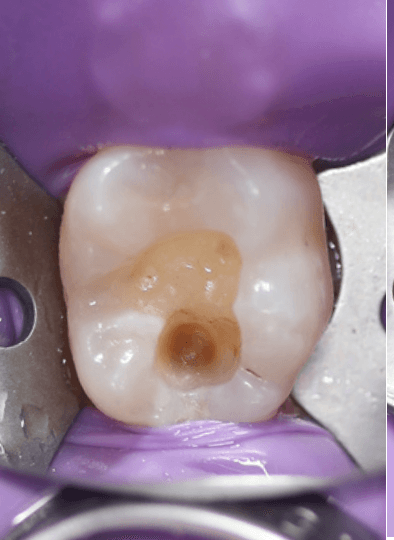

Existing restoration & caries removal

I use a highspeed and 541 to remove the restorations and open up the carious lesion. I used caries dye to assist accurate and conservative clearance.